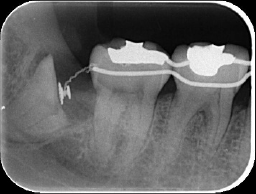

術直後 |

術後3週 |

術後7週 |

はじめに歯冠部だけを取り、矯正装置を装着し根っこの部分を引っ張り出します。